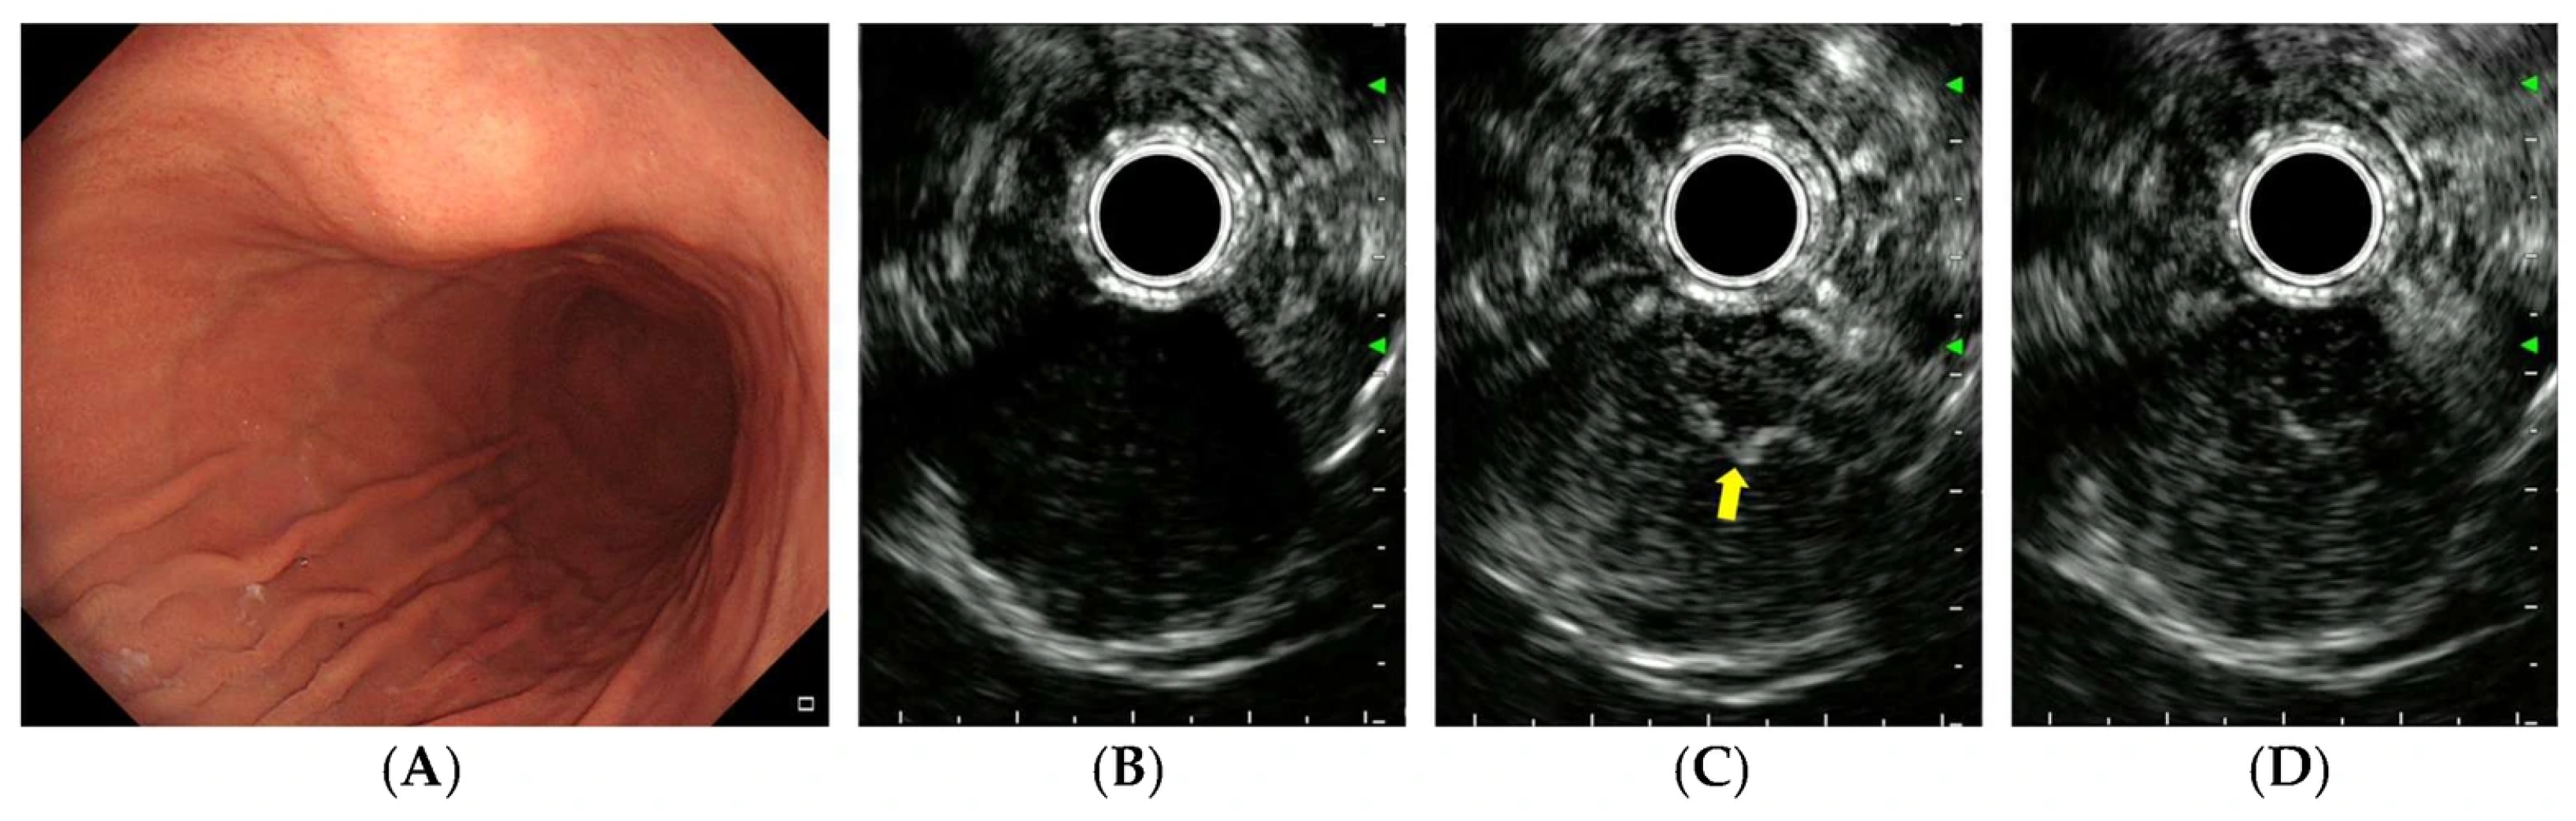

| Irregular vessels | 0.017 | ||

| Absent | 21 | 20 | |

| Present | 6 | 21 | |